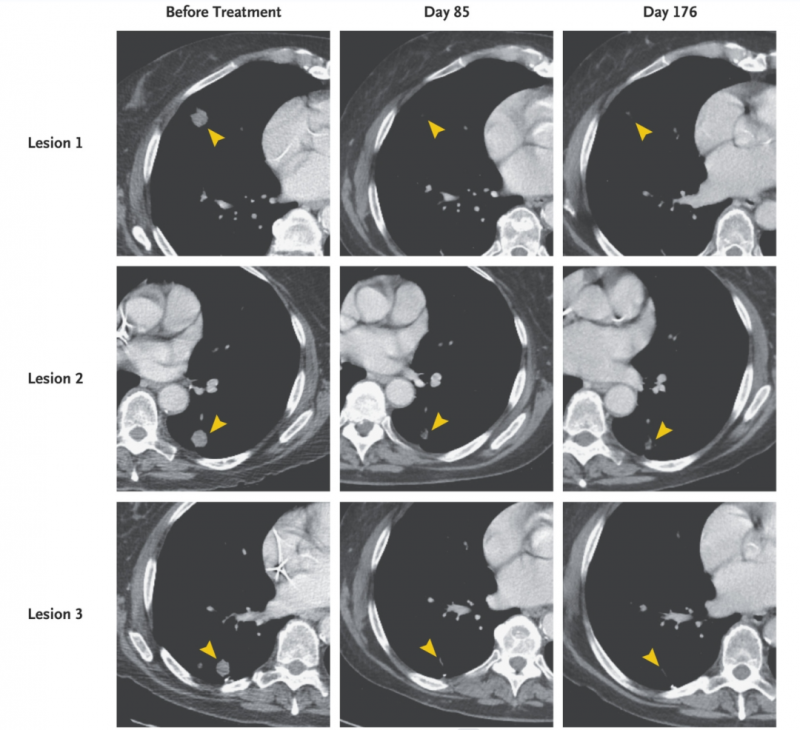

一例71岁进行性转移性胰腺癌患者,既往接受手术及放化疗后,病情持续进展,癌细胞已扩散至肺部。不过幸运的是。该患者基因检测发现,体内存在一种“KRAS”的突变蛋白,这也为该患者后续接受靶向KRASG12D的TCR-T治疗,提供了可能。患者入组后,见接受了托珠单抗+环磷酰胺的预处理治疗,之后再接受TCR-T治疗。

结果显示,TCR-T治疗后第21天,患者的血小板计数和绝对中性粒细胞得以恢复;治疗第1个月的计算机断层扫描显示,患者肺转移病灶消退;治疗后6个月,部分缓解(PR)率高达72%!

图1 胰腺癌患者TCR-T治疗前后,胸部计算机断层扫描对比图

▲图源“NEJM”,版权归原作者所有,如无意中侵犯了知识产权,请联系我们删除